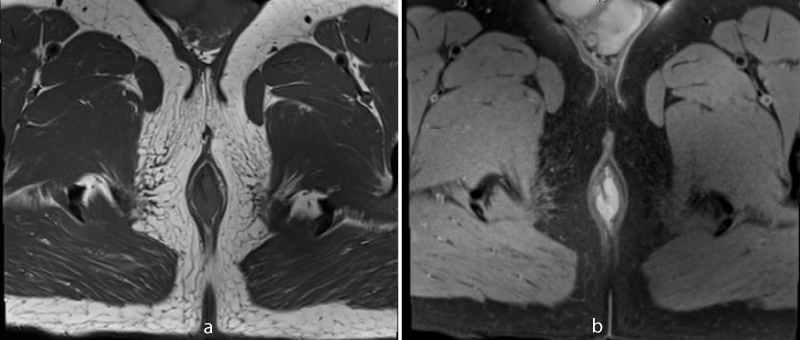

MR imaging revealed short segment circumferential wall thickening of the anal canal with lower margin approximately 1.7cm from anal verge. It was nearly 3 cm in length and 7mm in maximum thickness. The wall thickening showed hyperintense signal in T1-weighted images and T2-weighted images (Figures 1-3). Restricted diffusion with corresponding low signal in ADC map was noted figure 4. Post gadolinium T1-weighted fat saturated images showed hyper enhancement of the wall thickening (Figure 5). The thickening was involving the internal sphincter. No invasion of intersphincteric plane and external sphincter was noted. No extension into perianal fat was noted. Few enlarged heterogenously enhancing lymph nodes were noted in right inguinal region largest 23 x 21 mm in size. The patient underwent wide local excision with right inguinal dissection and adjuvant loco-regional radiotherapy. The histopathological examination showed features suggestive of primary anal malignant melanoma (Figure 6). In routine follow up, the patient showed no features of local recurrence or distant metastasis.

Figure 1: 60 year old male with primary anal melanoma. Axial T1-weighted MR image without fat saturation (a) and with fat saturation (b) shows circumferential hyperintense wall thickening in anal canal.

Figure 2: Axial T2-weighted MR image also shows hyperintense signal of the wall thickening.